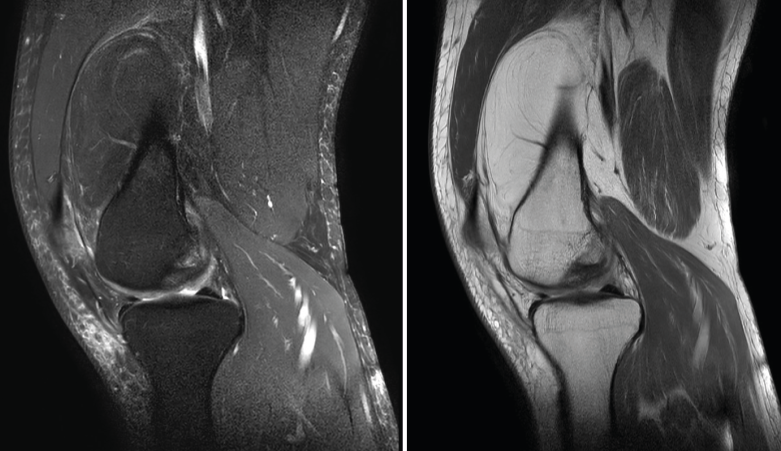

La RM es la técnica de elección en el diagnóstico de la patología meniscal(17)(Figuras 30, 31, 32, 33, 34 y 35).

Figura 35. Corte de secuencia coronal y sagital de resonancia magnética de rodilla: rotura en asa de cubo del menisco interno con fragmento desplazado al intercóndilo.

1.2. Ligamentos

Se visualizan como estructuras lineales hipointensas en todas las secuencias.